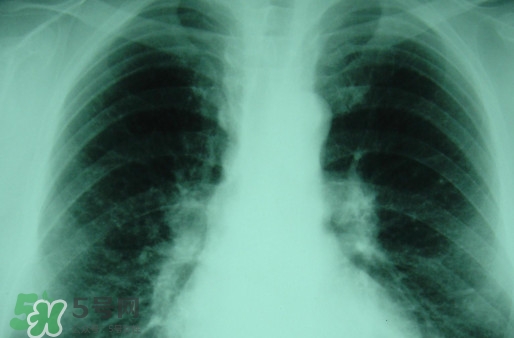

對(duì)于塵肺病,很多人都是陌生而又熟悉,因?yàn)槠渚褪且环N人體肺部滿身灰塵的病癥,一般從事煤礦或是珠寶打磨行業(yè)人群患病率高。那么,塵肺病能治愈嗎?塵肺病能活多久?

塵肺病受制于現(xiàn)行的醫(yī)療技術(shù),目前塵肺病是無法徹底治好的。

輕微患者可以考慮洗肺,重癥患者建議采取保守治療。

塵肺病屬于不可逆疾病,一定要及時(shí)及早治療!